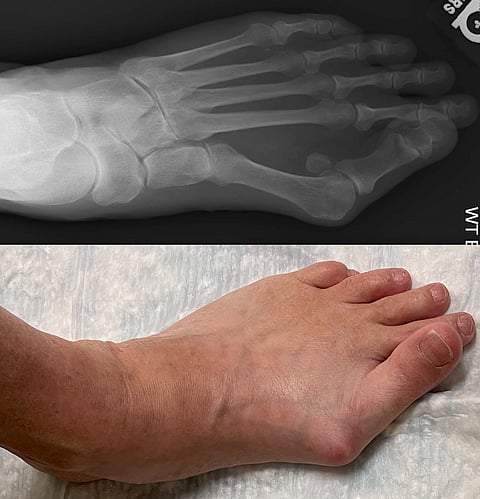

Pre-operation images of a bunion Images: UT Southwestern

Bunions form on the base of the big toe when the long metatarsal bone shifts toward the inside of the foot and its phalanx bones angle toward the second toe. As the soft tissue of the foot rubs up against shoes, pain results.